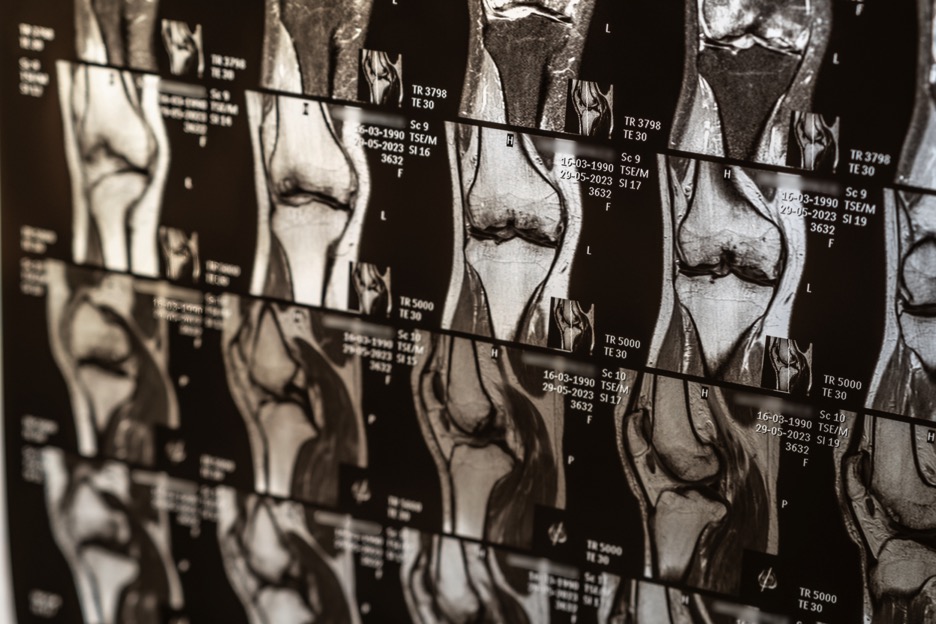

Además, se solicitan radiografías para evaluar desgaste o cambios articulares. La resonancia magnética puede utilizarse cuando ayuda a confirmar el diagnóstico o a decidir si el tratamiento debe ser conservador o quirúrgico.